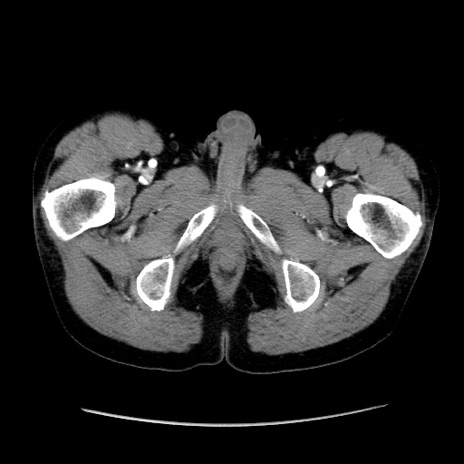

症例37(横断像)

【症例】40歳代 男性

【主訴】腹痛

【現病歴】4時間ほど前に電車に乗車中に臍部上より腹痛出現。徐々に増悪し起立困難となり、救急外来受診。生ものは数日食べていない。今朝お雑煮を食べた。

【身体所見】BT 36.8℃、BP 117/84mmHg、HR 91/min、SpO2 97%、苦悶様、腹部:臍上部広範囲圧痛あり、反跳痛±

【データ】WBC 8100、CRP 0.03